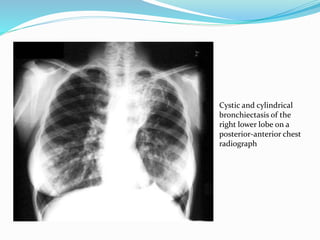

Cystic and cylindrical

bronchiectasis of the

right lower lobe on a

posterior-anterior chest

radiograph

Radiography P-A andlateral chest radiographs should be taken. Expected findings : 1. Increased pulmonary markings 2. Honey combing 3. Atelectasis 4. Plueral changes Specific findings – Tram –tracking, dilated bronchi, clustered cysts.